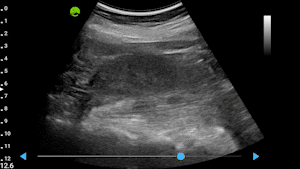

Real-Time Visual Guidance

Dynamic, multi-planar probe positioning assistance overlaid directly on the ultrasound image

Automatic Quality Assessment

Real-time quality scoring with percentage indicators ensures every captured image meets diagnostic standards

Smart Auto-Capture

Hands-free recording automatically captures clips when optimal image quality is achieved

View Recognition & Validation

AI identifies and validates standard cardiac and OBG views, ensuring protocol compliance